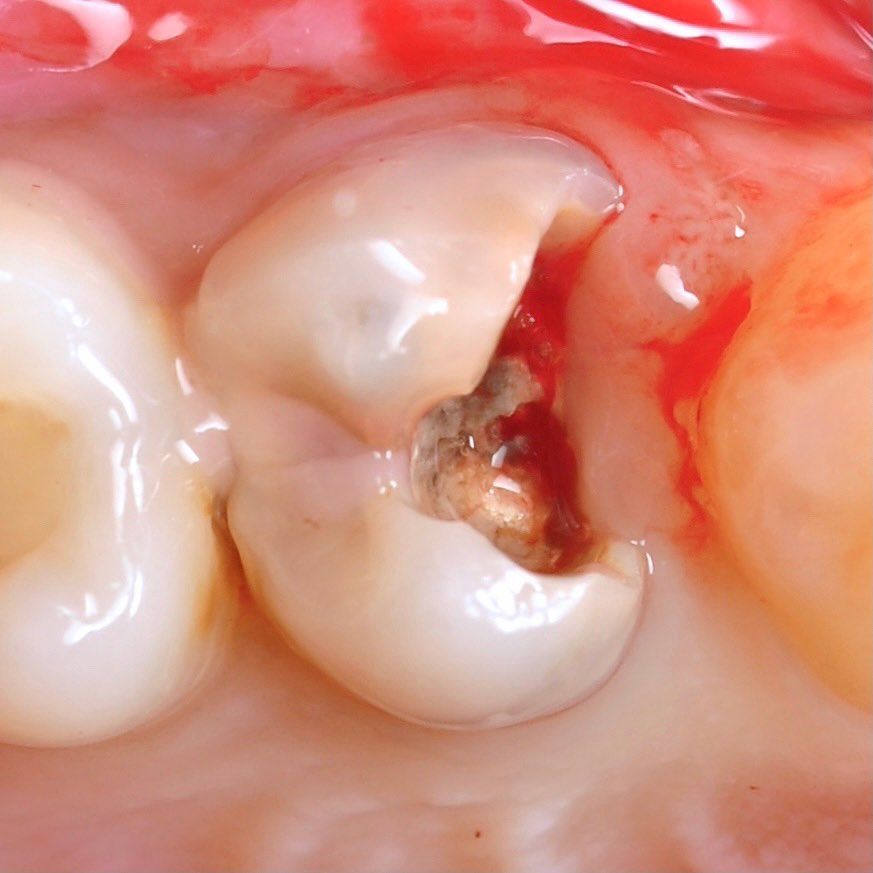

careful treatment of canals

Accurate determination of the geometry of the channels and their high-quality processing

caries removal

channel processing